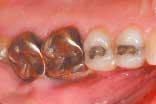

The upper and lower occlusal shots, as well as the four individual quadrants, are captured next. The four individual quadrant shots are the most powerful of the series. These are the shots where a patient can see old restorations, wear facets, recurrent decay, poor contour, etc. It is with the quadrant shot that the patient asks for dentistry. The doctor does not need to sell it!

Laboratory communication is perhaps the most important part of digital camera ownership. Traditionally, we have taken images of patients' teeth to communicate to our laboratory the shade and texture of the teeth for an indirect restoration. This is still a great application for digital cameras. The advantages of using a digital medium include the following:

Taking images of every indirect restoration will become routine. There is no reason not to take an image of every restoration. Laboratory technicians often are given only a set of stone models on which to build your restoration. When they have an image to go by, the quality of the restoration will be improved immeasurably. Patients will perceive that you are a high tech fastidious dentist who is going to give them a superior product.